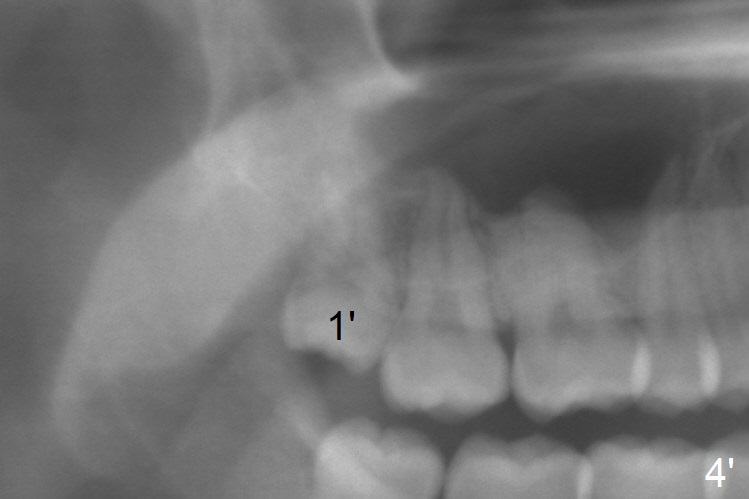

Panoramic X-ray is taken immediately post extraction of one of the upper right 3rd molars (Fig.3,3') and 20 months postop (Fi.4,4').  In fact the remaining one has erupted normally.